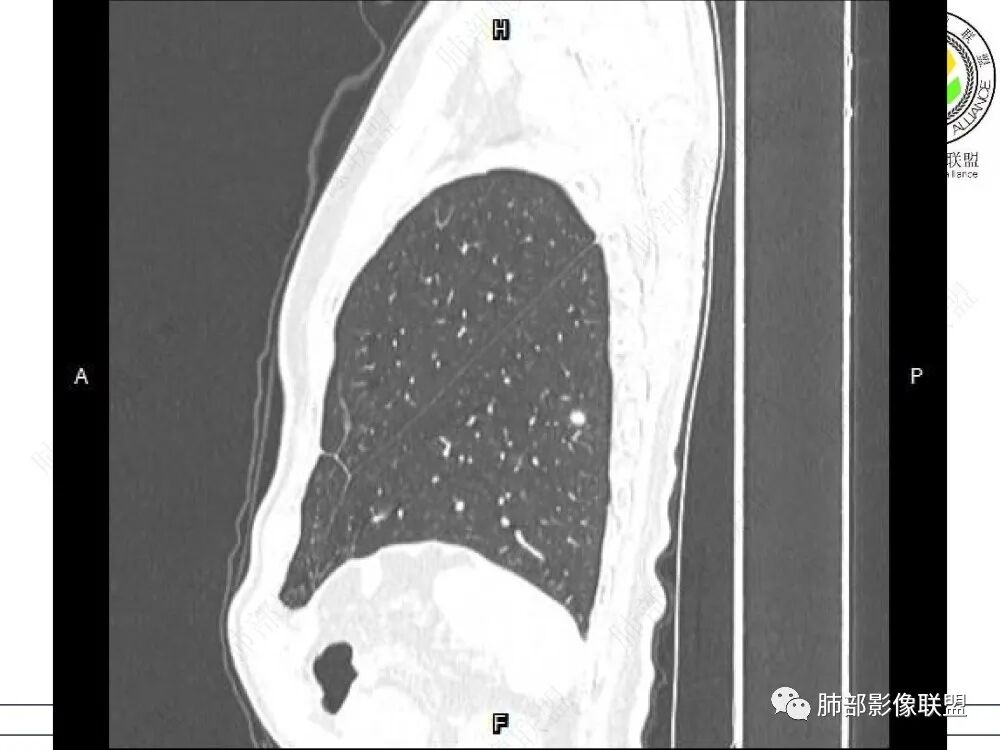

1、临床特点:中老年男性,间断左侧胸痛2年余,复发1月余,既往左肺上叶占位穿刺确认肺腺癌,未行手术治疗,给予两次射频消融术,术后定期复查,1月前患者出现左下胸部阵发性刺痛,无畏寒、发热、咳嗽等其他临床症状,门诊胸部CT提示:左肺下叶新发结节。

2、影像特点:左肺上叶尖后段病灶结合病史考虑消融术后改变,双肺下叶胸膜下可见多发大小不等的实性结节,周围似乎有晕,边缘平直为主,未见深分叶,部分可见邻近胸膜牵拉,张力不高,增强后呈轻中度强化。

3、总结:中老年男性,间断胸痛就诊,余无明显其他临床体征。既往肺癌病史,定期复查,一年左右双肺新发多发结节,常规需要鉴别炎性肉芽肿和肺癌转移。病灶以胸膜下为主,边界清楚,尽管转移是可以的,但混合磨玻璃时期腺癌相对惰性,短期内难以出现如此转移灶。况邻近胸膜牵拉,这在转移中也相对要少见。病灶多发,但没有新旧不等,没有树芽,病灶及时间线不支持继发性肺结核。病灶散在,胸膜下为主,周围可见少许晕征,部分病灶边缘比较平直,影像上较为符合隐球菌等肉芽肿性炎。